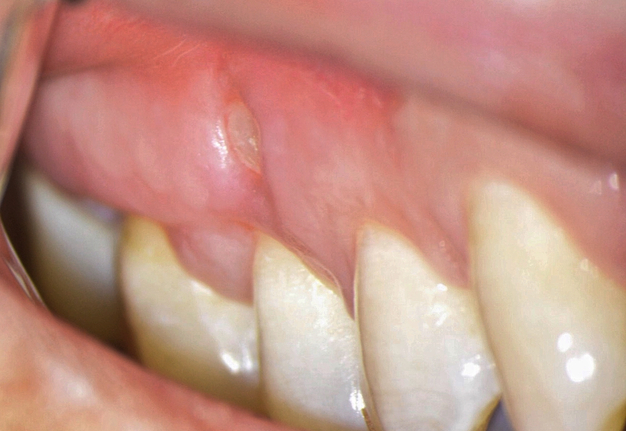

One of the less well-described, rare and late complications of the Ochsenbein-Luebke incision is the occurrence of fenestrations in the soft tissues with baring bone. These fenestrations can be located both in the area of ​​the attached gingiva, which corresponds to the horizontal component of the incision (Fig 15), and on the transition of attached gingiva into the alveolar mucosa, which corresponds to the vertical component of the incision (Fig 16).

The development of soft tissue fenestrations with associated bone exposure is predominantly linked to a thin gingival biotype, suboptimal flap design, and inadequate wound closure.